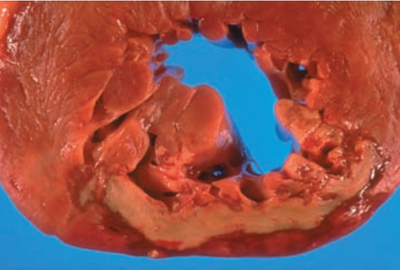

disoriented state. Physical examination reveals jaundice,

splenomegaly, and ascites. Serum levels of ALT, AST, alkaline

phosphatase, and bilirubin are all elevated. A liver biopsy